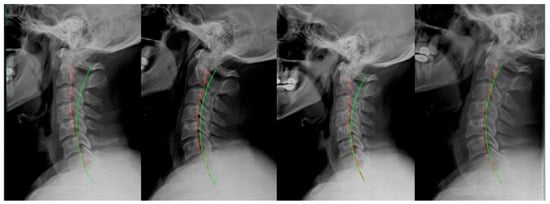

2. Materials and Methods

2.1. Case 1

2.2. Case 2

2.3. Case 3

2.4. Case 4